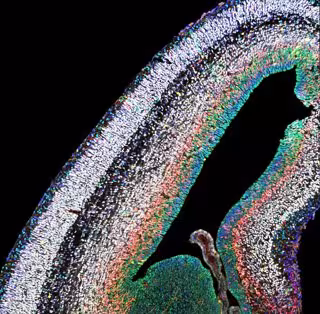

IST AUSTRIA / GRUPO HIPPENMEYER

Para construir el neocórtex, un área del cerebro involucrada en funciones cognitivas superiores, las células madre producen billones de neuronas de varios tipos. En un estudio científico, neurocientíficos de Suiza, Bélgica y el Instituto de Ciencia y Tecnología de Austria (IST Austria) han demostrado que, con el tiempo, las células madre neocorticales pasan por varios estados de maduración, cada uno de los cuales conduce a un tipo neuronal distinto. La producción del tipo de neurona correcta está unida a un complejo proteico específico.

Con sus profundos surcos y crestas, el neocórtex ha acuñado nuestra noción del cerebro humano. Con solo unos milímetros de espesor, esta capa cerebral externa contiene más de 15.000 millones de neuronas y procesa información para que podamos experimentar y percibir conscientemente el mundo. Obviamente, si algo sale mal durante el desarrollo de la neocorteza en el embrión, pueden ocurrir disfunciones graves asociadas con trastornos del desarrollo neurológico y psiquiátricos, como autismo o esquizofrenia.

El estudio presenta evidencia de que las células madre neurales en desarrollo están equipadas con programas específicos de expresión génica (transcripcional) en diferentes momentos. Mientras que las células madre progresan secuencialmente a través de distintas etapas, pasan estas "huellas dactilares" transcripcionales a sus células hijas, es decir, las neuronas que producen.

Sorprendentemente, las células madre parecen tener diferentes propiedades y expresión génica en distintas etapas durante el desarrollo neocortical: en las etapas iniciales, las células madre tienden a estar equipadas con programas que regulan principalmente los procesos celulares internos, como el control del ciclo celular. En contraste, durante las etapas posteriores, las células madre mantienen programas de expresión génica que requieren cada vez más señales externas y, por lo tanto, interacción ambiental.

La inactivación de PRC2 tuvo consecuencias drásticas de una manera que las células madre no pudieron seguir su camino normal de maduración. En ausencia de PRC2, las células madre parecían madurar demasiado rápido y, por lo tanto, producían tipos incorrectos de neuronas durante falsas ventanas de tiempo.

Aún más dramático fue que el número total de neuronas producidas también se redujo drásticamente. Esto dio lugar a una pequeña corteza, también conocida como microcefalia, con una composición de tipo celular neuronal incorrecta. "Los resultados ilustran lo sensible que es el desarrollo cerebral. Ahora tenemos una idea más clara de cómo las células madre neurales producen el tipo y número correctos de neuronas durante el desarrollo cortical, lo que podría ayudar a comprender mejor los mecanismos subyacentes de la malformación del cerebro humano y los trastornos del desarrollo neurológico en general", concluye Nicole Amberg, que recientemente recibió una beca FWF Hertha-Firnberg.